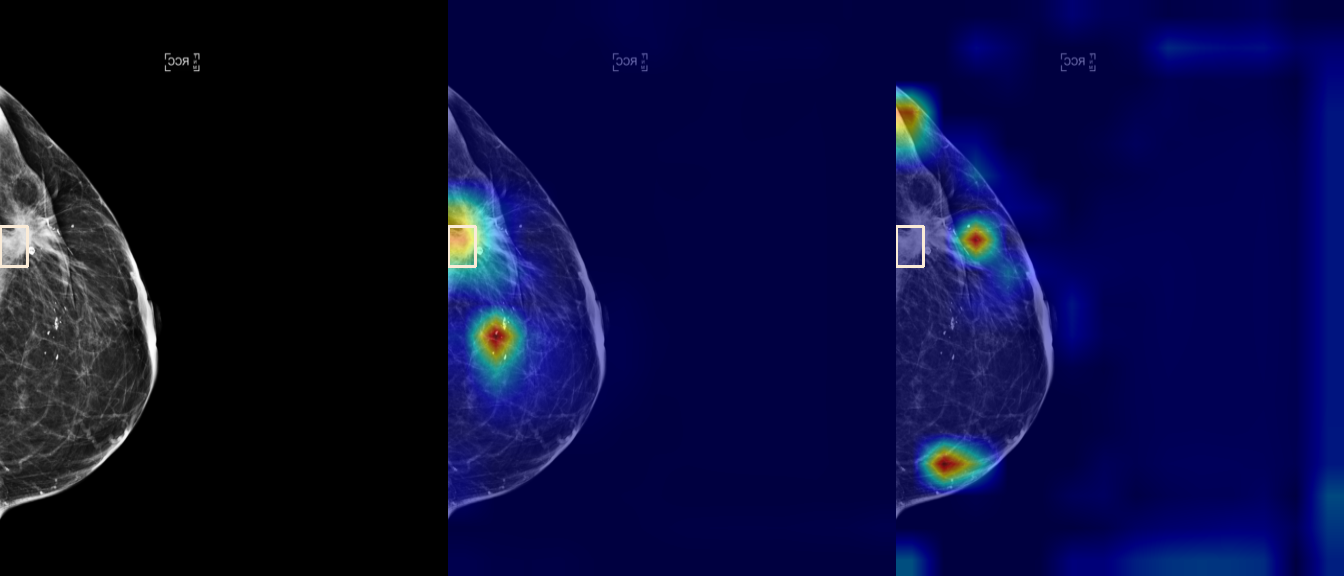

To interpret the decision-making process behind the quantitative results, we visualized Class Activation Maps (CAM) for the top-performing methods, ERM and VREx. Figures 1 through 2 illustrate discriminative regions identified by the models within the full mammograms.

Localization of Clinical Features: A key concern in medical AI is whether high performance stems from genuine pathology detection or spurious background correlations. Our visualizations suggest that Standard ERM achieves its superior quantitative performance by predominantly prioritizing clinical cues. As shown in the top rows of the Figure 1 and Figure 2, the ERM-trained models consistently focus attention on the specific lesion regions within the breast tissue. This demonstrates that despite lacking explicit invariance constraints, ERM is capable of learning robust, medically relevant features when trained on diverse multi-source data.

Attention Drift in Both Methods: While both ERM and VREx generally identify the correct region of interest in successful cases, neither method is immune to attention drift. We observe instances in both training paradigms where the model focuses on irrelevant areas, such as healthy fibroglandular tissue or background artifacts (e.g., rows 5 and 6 in Figure 1). This indicates that while VREx is designed to penalize instability, it does not guarantee perfect anatomical focus compared to the unconstrained ERM baseline.